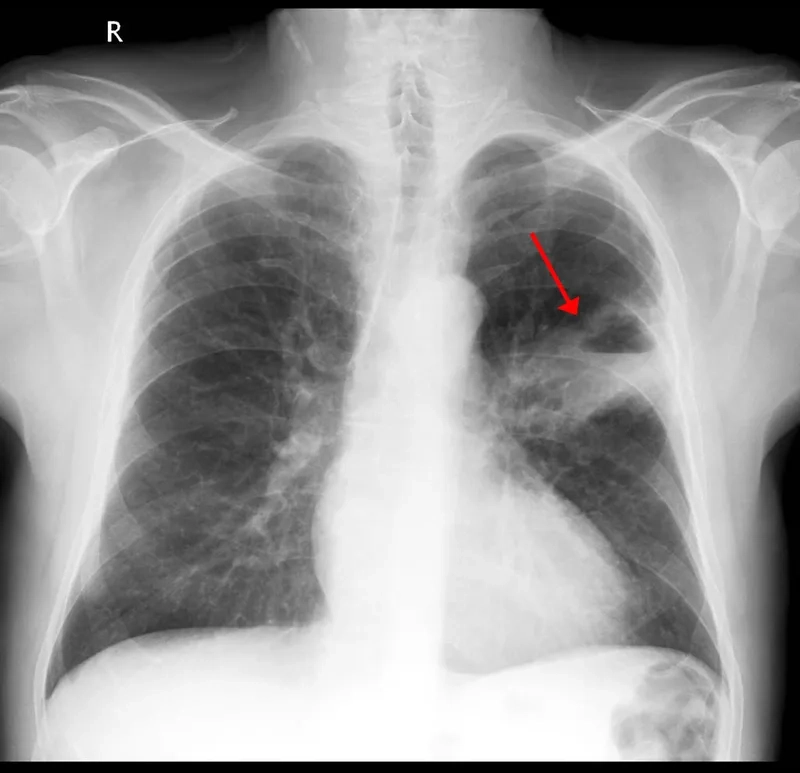

• As the cancer progresses through different lung cancer stages, symptoms may include bone pain, headaches, and shortness of breath.

Early detection through screening is critical for improving the lung cancer survival rate. If you have risk factors or symptoms, consult your doctor about diagnosis and treatment.